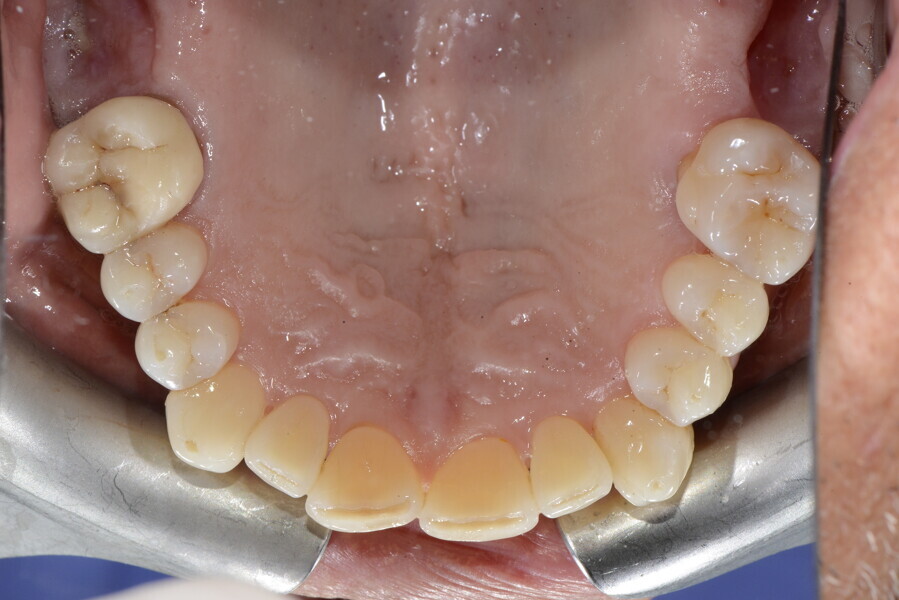

The 58-year-old patient wished to improve his oral aesthetics and function, complaining of mobility of the posterior teeth and wear of the anterior teeth. After data collection, a very complex situation was identified (Figs. 11–13):

1. severe periodontitis with poor prognosis of some teeth;

2. anterior crossbite;

3. severe wear mainly of the anterior teeth and compensatory eruption;38

4. atypical swallowing and lower posture of the tongue at rest;

5. masticatory dysfunction during the mastication test; and

6. no significant signs of temporomandibular disorder.